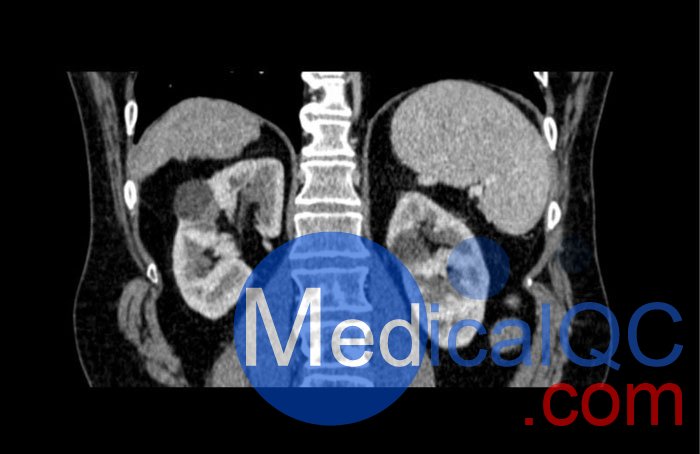

WEK53-04肝硬化腹部模體,WEK53-04門靜脈期腹部模體詳細(xì)介紹:

WEK53-04肝硬化腹部模體,WEK53-04腹部模體模擬了門靜脈期的造影劑增強(qiáng)腹部。它覆蓋了第十胸椎至第三腰椎。

WEK53-04肝硬化腹部模體,WEK53-04腹部模體代表膽囊切除術(shù)后的腹部,帶有小夾子。肝臟有肝硬化的典型體征,在第三腰椎水平植入下腔靜脈過濾器。兩個(gè)腎臟都有囊性病變,左側(cè)有一小塊腎結(jié)石。

該模型可用于 CT(包括 CBCT)以評(píng)估和優(yōu)化成像性能和后處理應(yīng)用,包括支持 AI 的應(yīng)用。它也適用于培訓(xùn)目的。

該模型提供了對(duì)軟組織和骨組織的詳細(xì)而逼真的模擬??障吨刑畛渲s-160HU的纖維素-聚合物復(fù)合材料。

WEK53-04肝硬化腹部模體,WEK53-04門靜脈期腹部模體診斷特征

真實(shí)模擬脈管系統(tǒng)、骨骼和軟組織,包括肝臟、胰腺、脾臟、腎上腺、腎臟、胃、小腸和結(jié)腸。

• 肝硬化

• 膽囊切除術(shù)

• 下腔靜脈濾器

• 腎囊腫

• 腎結(jié)石

• 淋巴結(jié)腫大

WEK53-04肝硬化腹部模體,WEK53-04門靜脈期腹部模體產(chǎn)品成像圖:

SAG: